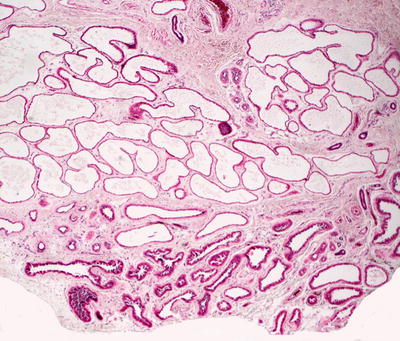

23.6.2 Histology

Being true epidermal inclusions cysts, dermoid cysts contain all epidermal components. Within the mid-reticular dermis, a cystic cavity that is often filled with keratin is apparent. The cyst wall is lined by stratified squamous epithelium, complete with a granular layer. Pilosebaceous units emanate from the cyst lining into the surrounding dermis (Figs. 23.10 and 23.11). Apocrine and eccrine ducts are present, and smooth muscle bundles are seen in a minority of cases. In some dermoid cysts occurring close to the eyes, conjunctival type mucosa with goblet cells have been reported in the cyst lining [30]. When the cysts have been traumatized, a granulomatous foreign body giant cell reaction may ensue [31]. Late lesions may flatten and only dense fibrosis is apparent in senescent lesions [32].

Fig. 23.10

A dermoid cyst demonstrates squamous epithelium, keratinaceous cyst contents, and cutaneous appendages in the wall of the cyst

Fig. 23.11

Vellus hairs, squamous epithelial lining, and cutaneous appendages in the cyst wall are seen in dermoid cysts